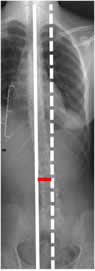

Desbalance sagital:

Se mide en la proyección lateral, determinando la distancia que existe entre la vertical que cruza por la mitad del cuerpo de C7 y la línea que pasa por el borde posterior superior de S1. (25, 26). (Fig 35).

Normalmente la distancia también es menor de 2 cm. Se habla de balance positivo cuando la distancia es mayor de 2 cm, por delante del sacro y negativo, cuando se localiza por detrás del sacro. (25, 26). (Fig 36 y 37).

Fig 35. Balance sagital normal.

Rx lateral. Línea vertical normal, que pasa por la mitad del cuerpo de C7 y coincide con el borde posterior superior el sacro.